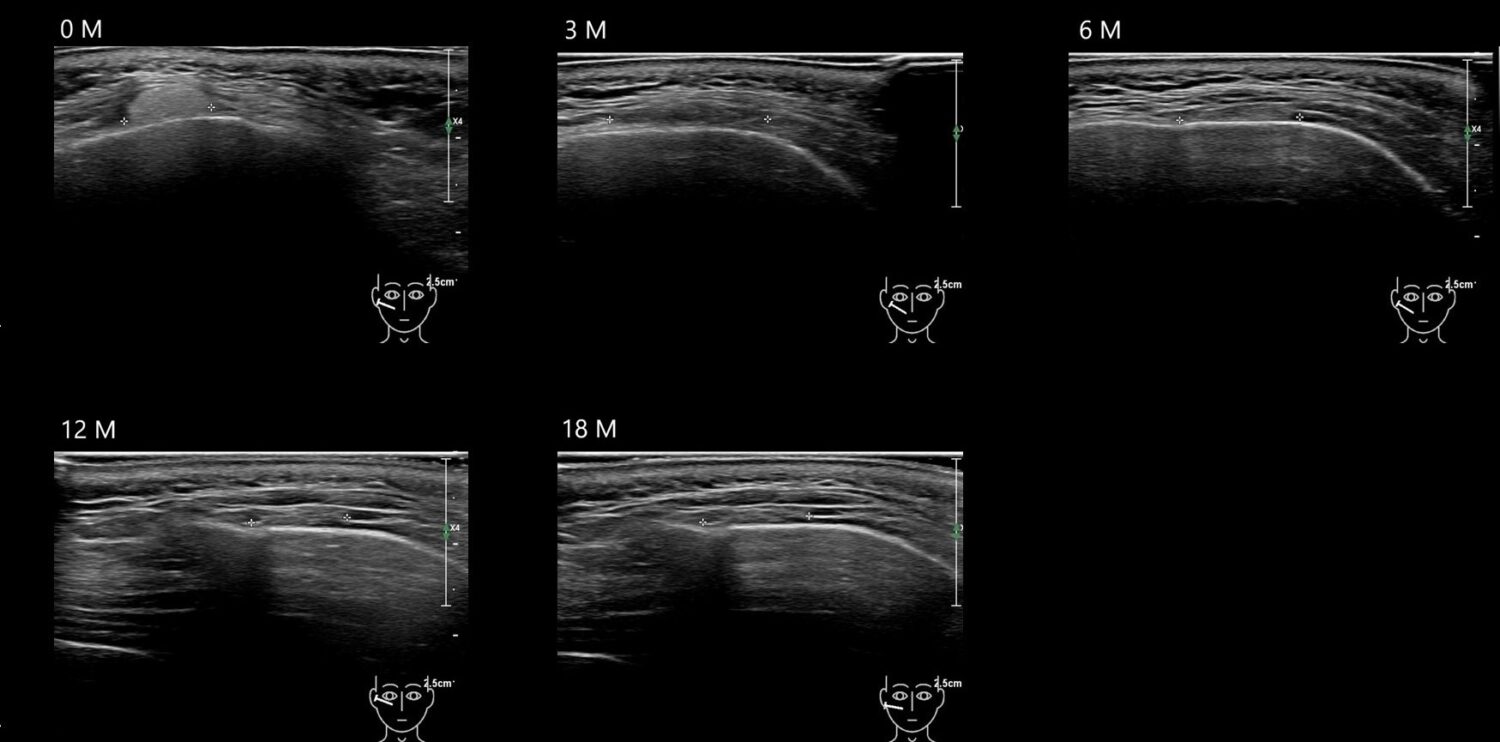

Draw in the image on the right where the fillers are located. To check if your answer is correct, please click on the secondary image.

Draw in the second image below where the fillers are located. To check if your answer is correct, swipe the first image to the right.